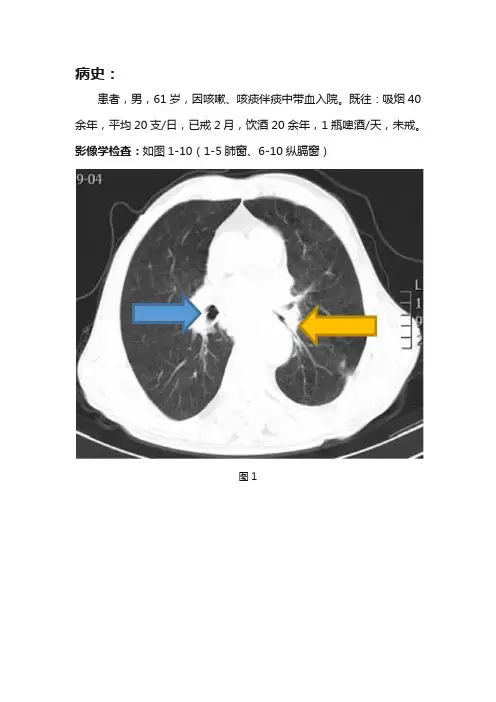

病史:患者,男,61岁,因咳嗽、咳痰伴痰中带血入院。

既往:吸烟40余年,平均20支/日,已戒2月,饮酒20余年,1瓶啤酒/天,未戒。

影像学检查:如图1-10(1-5肺窗、6-10纵膈窗)图1图2图3图4图5图6图7图8图9图10基础解剖影像:图11图12图13图11-13所示为正常人纵膈窗增强静脉期轴位,显示纵膈内强化血管影、气管、支气管、食管、胸腺、肋骨、肌肉影,可见主动脉弓(黄色箭头)、上腔静脉(蓝色箭头)、肺动脉主干(绿色箭头)、升主动脉(棕色箭头)、左心室(白色箭头)。

右主支气管及分支气管走行未见异常(蓝色箭头),左主支气管及分支支气管管壁增厚,管腔狭窄(黄色箭头),左肺门影增大,纵膈内气管隆突下(白色箭头)、食管旁(灰色箭头)、主动脉弓旁(棕色箭头)可见多个结节样、团块状软组织密度影,融合成团,食管中下段受压变窄,上段扩张并积液(紫色箭头)。

影像诊断:左主支气管、肺门及纵膈内改变,考虑左肺中心型肺癌,伴肺门、纵膈淋巴结转移,食管继发改变。